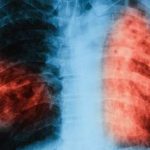

Some of the most commonly used and familiar diagnostic tests using chest X-rays and or growing the bacterium in culture, are more than 100 years old. Although changes seen on a chest X-ray might suggest TB disease, these changes do not prove that the patient has TB disease or give an indication if the TB bacteria are resistant to the commonly used anti-TB antibiotics. Although the culture of TB bacteria from the sputum of a person with TB disease is an accurate diagnostic test, it also has a numerous weaknesses. TB culture is expensive and can take up to 6 weeks before it is known to be positive but once the bacteria have been grown in culture it can then be tested for resistance top various drugs. This is not acceptable as the disease will advance during the delay and the person will continue spreading TB in their household and community. In patients with severe suppression of their immunity, including people infected with HIV-infected persons the TB disease may spread so rapidly that the patient may die while waiting for their test result. The low sensitivity of chest X-rays and TB culture tests leads to the need to treat ‘presumptively’. Presumptive TB is diagnosed when on assessing the signs and symptoms of TB, night sweats, sudden weight loss, persistant coughing or blood in the sputum, the doctor feels that the diagnosis of TB disease is highly likely even though there is no definitive proof that the patient has TB disease. The diagnosis is based on a risk benefit analysis when the risks of harm from the unnecessary use of the TB drugs are outweighed by the risk of not treating actual TB disease. The problem with this approach is that a high proportion of patients are unnecessarily treated for TB; estimated to be between 20% to 40% and this is no small matter as the anti-TB drugs have to be taken for 6 months with have numerous unpleasant side effects.